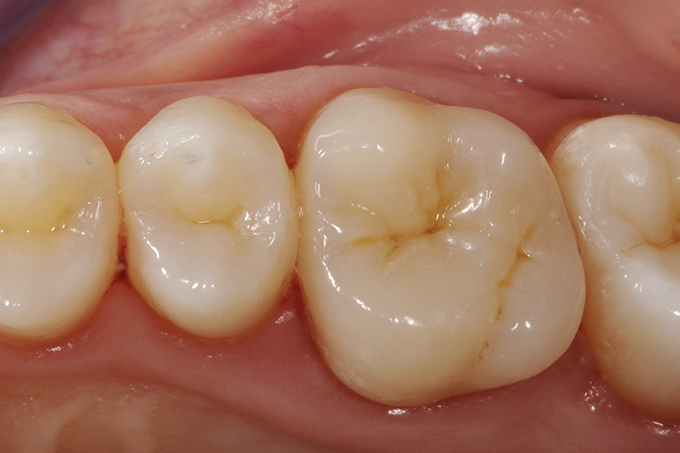

Initial situation: The patient was complaining about the lack of a contact point to the neighboring tooth. She was suffering occasional pain while chewing.

Overlay immediately after cementation with natural teeth still dehydrated.

Check-up - 15 days after successful reconstruction.